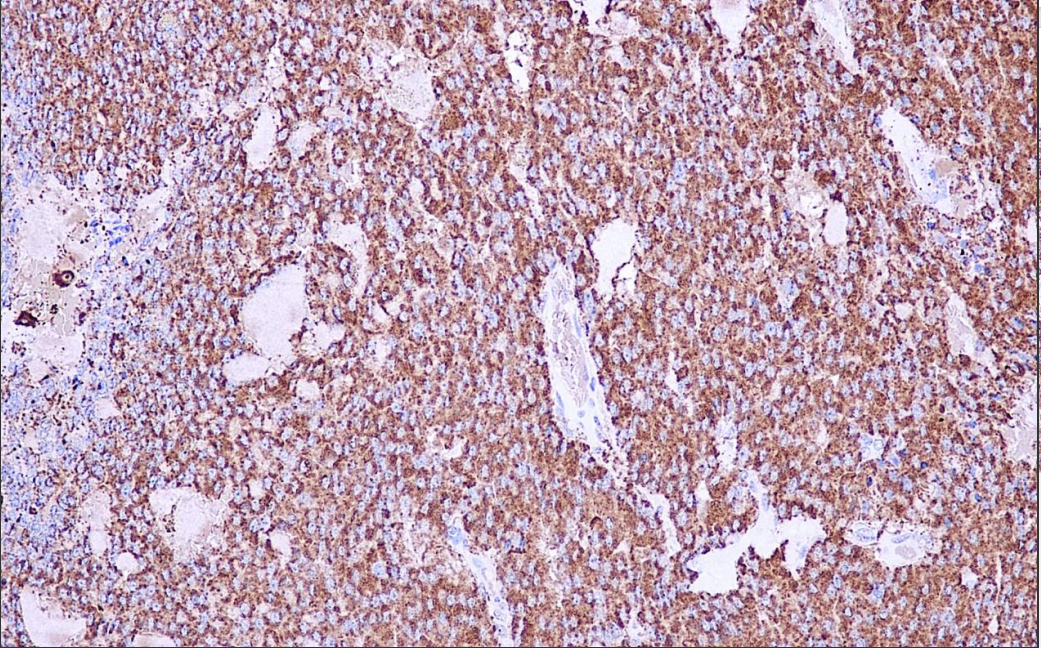

Positive control: medullary thyroid carcinoma

Calcitonin is secreted by parafollicular thyroid cells (C-cells), with a molecular weight of 350 kDa, and has the function of lowering the level of calcium in the blood.Calcitonin Antibody is mainly used in the study of C-cell hyperplasia, medullary carcinoma of the thyroid, parafollicular follicular carcinoma of the thyroid, and some neuroendocrine tumors.

Calcitonin Calcitonin Antibody Reagent binds specifically to the Calcitonin molecular antigen. Immunohistochemistry kits containing Calcitonin Antibody Reagent are indicated for the precise diagnosis of C-cell hyperplasia, medullary carcinoma of the thyroid, parafollicular follicular carcinoma of the thyroid, and selected neuroendocrine tumors.